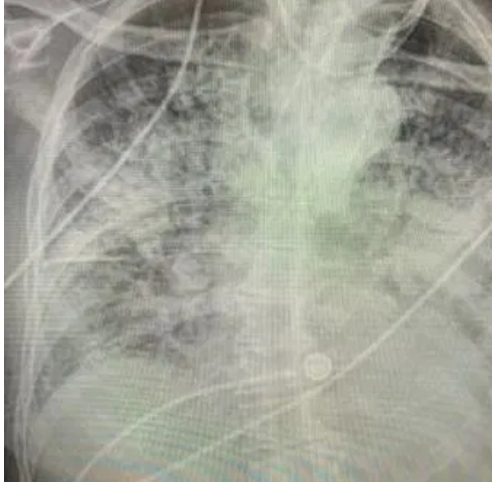

Как пишет Тhe Sun, впечатляющими снимками поделилась доктор Бриттани Бэнкхед-Кендалл, доцент Центра медицинских наук Техасского технологического университета, которая вылечила тысячи пациентов с коронавирусом.

Одно изображение показывает нормальную здоровую пару легких, другое - легкие курильщика, а третье - легкие пациента с коронавирусом.

"Легкие после коронавируса выглядят хуже, чем любой тип легких ужасного курильщика, который мы когда-либо видели. Они разрушаются. И они слипаются. И одышка сохраняется", - сказала доктор.

Бриттани Бэнкхед-Кендалл подчеркнула, что разрушительное действие Covid-19 на легкие заметно даже у тех пациентов, кто перенес его в легкой форме.

Она добавила, что пока неизвестно, заживут ли когда-либо рубцы, вызванные коронавирусом, но каждый, кто испытывает стойкую одышку, должен поговорить об этом со своим врачом.